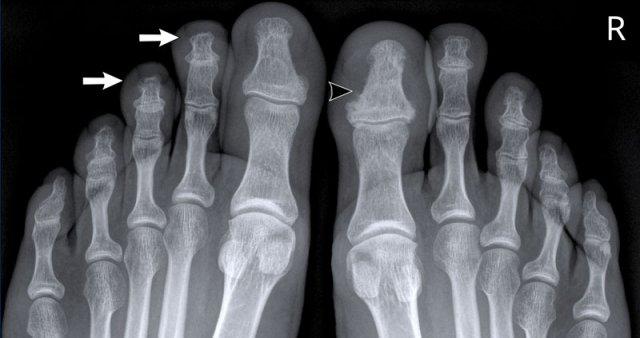

Trong trường hợp viêm khớp dạng thấp này, có hình ảnh bào mòn xương vùng rìa liền kề với hầu hết các khớp bàn ngón chân (MTP) (đầu mũi tên).

Khớp MTP thứ 5 là khớp bị tổn thương thường xuyên nhất trong viêm khớp dạng thấp.

Khi tình trạng bào mòn nặng nề như trong trường hợp này, hình ảnh có thể trông giống biến dạng “bút chì trong cốc” (mũi tên trắng) – dấu hiệu thường gặp trong viêm khớp vảy nến.

Tuy nhiên, phân bố tổn thương chủ yếu ở các khớp MTP và ít ảnh hưởng đến các khớp liên đốt là dấu hiệu gợi ý đây là trường hợp viêm khớp dạng thấp.